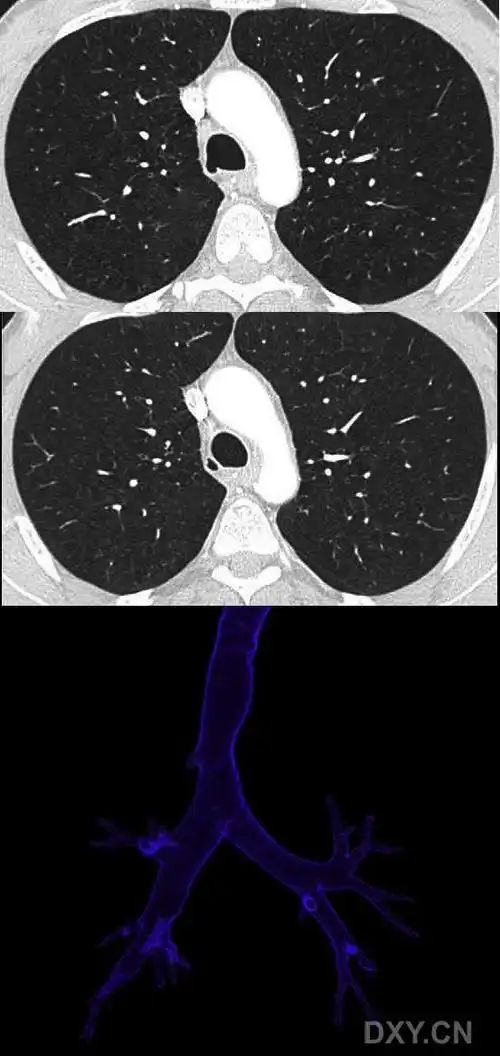

ct三维重建:观察右上肺占位组织是否存在变异血管,避免穿刺过程中损伤

图123‐3 气道三维重建

早诊早治肺结节ct三维重建技术带来诊治新突破

立体重建显示结节在胸腔的位置来自江西38岁的肺结节患者李女士(化名)

【影像读片】气管憩室ct三维重建 [病例帖]

整个肺部ct图像重建效果对比(其中一层)

3dslicer肺部影像三维重建及虚拟支气管镜